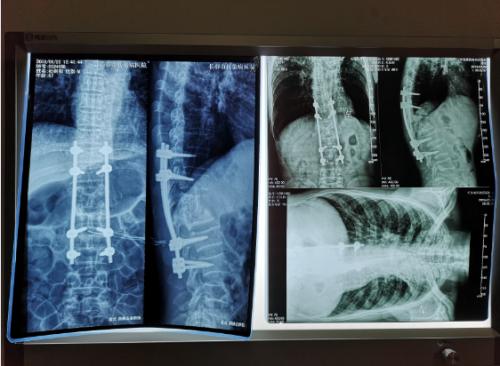

经过检查,罗坚主任凭着丰富的临床经验初步认为王大爷患的是胸椎结核伴脊髓压迫症,那么是什么原因造成的?通过脊柱磁共振检查,罗主任发现王大爷患胸椎脊髓压迫的元凶正是“骨结核”。王大爷胸椎骨7-11节被结核杆菌严重侵蚀,在重体力活后,胸椎脊髓神经受到压迫,最终导致下肢瘫痪。同时患者双肺结核伴左上叶不张,左侧胸腔大量积液。如果等待双肺结核治愈,需时日很长,脊髓的受压如果不能及时解除,导致脊髓变性,那么瘫痪就难以恢复了,在积极治疗肺结核胸腔积液引流,罗坚主任为王大爷尽快安排实施手术。

手术过程中,病人腰大肌脓肿巨大,病椎破坏重游离死骨多,结核物质使脊髓严重受压,既要侧前方减压清除病灶,又要完成后凸畸形的矫正,再由于王大爷年龄较大、体质差,风险高,对技术与手术期管理都是很大的挑战。

罗坚、陈松峰和任重三位医师组成的团队实施手术。罗坚主任凭借其多年外科生涯中大量胸椎结核手术所积累的丰富经验,在脊柱侧前方减压,病灶清除、植骨和后凸畸形矫正胸膜外操作。手术按计划顺利完成,而辗转数家医院的“求医记”终于告一段落,在外等候的家人听到手术成功的消息后喜极而泣。